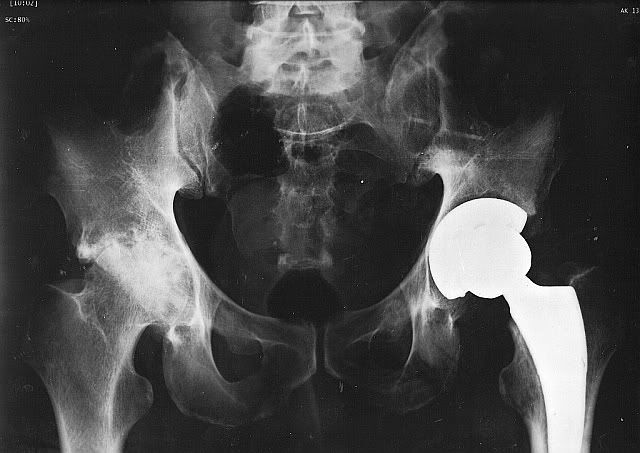

fioneczka Posted August 24, 2011 Author Posted August 24, 2011 mam zdjęcia odbiegające od tematu Monki biodra Krisa przed operacją lewa strona masakra i po operacji ... nówka sztuka nie śmigana ;) prawe niestety sypie się błyskawicznie mam nadzieję że to kiedyś skrzypieć nie zacznie :evil_lol: Quote

Kajusza Posted August 24, 2011 Posted August 24, 2011 pewnie w końcu poczuł ulgę ... no i sprawniej się porusza :-) rewelacja... a na prawe także będzie musiał mieć operację? Quote

fioneczka Posted August 24, 2011 Author Posted August 24, 2011 Kajusza napisał(a):pewnie w końcu poczuł ulgę ... no i sprawniej się porusza :-) rewelacja... a na prawe także będzie musiał mieć operację? no będzie, zasadniczo to ono już jest do roboty pytanie ile Kris wytrzyma , nie bardzo wiemy kiedy to będzie ... no i nie wiem czy to prawe też tak się uda "wyprosić" czy trzeba będzie "w kolejce stać" Quote

fioneczka Posted August 24, 2011 Author Posted August 24, 2011 Kajusza napisał(a):nie jestem lekarzem... ale skoro cierpi, bo to pewnie ból to po co czekać? Mam nadzieje, że nie ma uciążliwych dolegliwości. zanim nie będzie na tyle sprawny żeby używać lewej nogi w 100% to nie ma co myśleć o kolejnej operacji tak czy siak ... ile to czasu - nie wiem Quote

Alicja Posted August 24, 2011 Posted August 24, 2011 Nie wiem jak u Was ale u nas zapisują do kolejki już w czasie kiedy jest sie w okresie rekonwalescencji , znajoma czekała po 1szej operacji na drugą endo około 1,5 roku . Quote

fioneczka Posted August 24, 2011 Author Posted August 24, 2011 Alicja napisał(a):Nie wiem jak u Was ale u nas zapisują do kolejki już w czasie kiedy jest sie w okresie rekonwalescencji , znajoma czekała po 1szej operacji na drugą endo około 1,5 roku . Alunia w Zgorzelcu termin oczekiwania ok 7 lat we Wrocławiu byliśmy numerkiem 946 na liście oczekujących :roll: ile to lat - nie wiem :roll: Quote